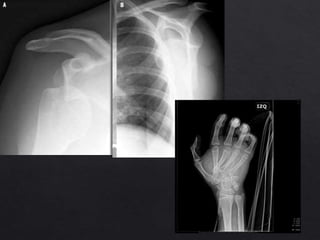

Luxación Gleno - Humeral

• Más frecuente del organismo

(45%)

• Gran mayoría son anteriores

(85-90%).

• Las posteriores son raras,

(asociadas a crisis

convulsivas y descargas

eléctricas).

– TAC: permite una mayor definición de

lesiones óseas periarticulares.

• Lesion de hill sach: defecto posterolateral de la

cabeza humeral por impacto en la glena.(27%

de luxaciones anteriores agudas y 74% de las

recidivantes)

• Defectos en el labrum glenoideo anterior:

lesiones de Bankart.

• Cuerpos libres intrarticulares.